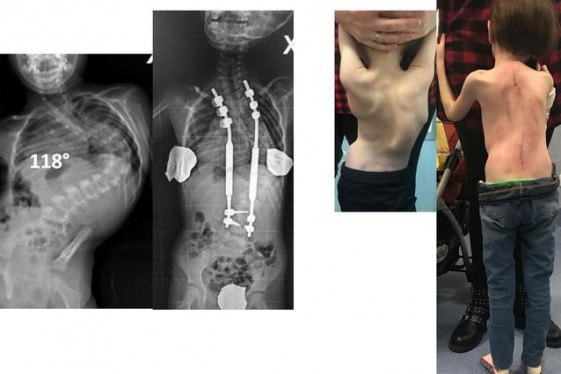

READ MOREA five-year-old girl suffering from a rare form of scoliosis has been cured with magnets in a first for Italy. The girl, who weighed just 11 kg (24 pounds, or one stone 10 pounds), presented with a form of the disease that had never been diagnosed before. She was operated on at Turin's Regina Margherita Hospital. For the first time in such a case,...